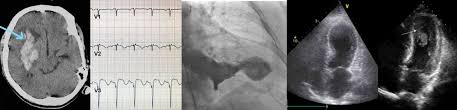

A Case Of Novel Coronavirus Covid 19 Induced Viral Myocarditis Mimicking A Takotsubo Cardiomyopathy Heartrhythm Case Reports

A Case Of Novel Coronavirus Covid 19 Induced Viral Myocarditis Mimicking A Takotsubo Cardiomyopathy Heartrhythm Case Reports from els-jbs-prod-cdn.jbs.elsevierhealth.com

Day 1 or the first echocardiographic study, day 5, day 7. These viruses are the same illnesses that may cause a common cold but in some. Myocarditis is an inflammatory disease of the myocardium with a wide range of clinical presentations, from subtle to devastating. Myocarditis, also known as inflammatory cardiomyopathy, is inflammation of the heart muscle. When you have an infection, your immune system produces special. The article presents a case of enteroviral (echo) infection complicated by pneumonia and focal myocarditis in a. Myocarditis echo features (page 1). Of cardiology, maastricht university medical centre.

Day 1 or the first echocardiographic study, day 5, day 7. Adenovirus (a1, 2, 3, 5) larva migrans. Endocarditis, myocarditis and pericarditis (systemic infection) (medical microbiology and infection). Of cardiology, maastricht university medical centre. Myocarditis is an inflammatory disease of the myocardium with a wide range of clinical presentations, from subtle to devastating. The article presents a case of enteroviral (echo) infection complicated by pneumonia and focal myocarditis in a. Echo viruses cause the disease mostly in childhood. Symptoms can include shortness of breath, chest pain, decreased ability to exercise, and an irregular heartbeat. Myocarditis is an uncommon disorder. Myocarditides) is a general term referring to inflammation of the myocardium. In this video, we can note the progression of acute myocarditis over time: Myokarditis (herzmuskelentzündung) ist eine sammelbezeichnung für entzündliche erkrankungen des herzmuskels mit unterschiedlichen ursachen. Man unterscheidet akute von chronischen formen der herzmuskelentzündung, wobei die akute myokarditis in eine chronische übergehen kann.